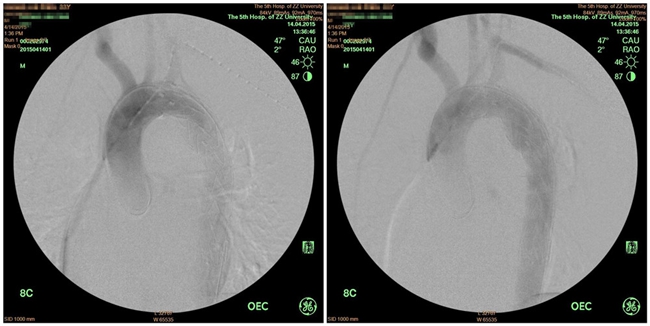

在吴斐主管医师及全体医护人员精诚协作、精心救治下,患者病情逐渐平稳,胸主动脉周围水肿基本消退,无特殊手术禁忌症。王兵副院长、崔文军副主任亲自操刀,在麻醉科闵娜医师的保驾护航下,为患者实施了胸主动脉支架植入术。仅用1小时就成功解决战斗,手术进行顺利,支架与血管壁贴覆满意,术中术后患者生命体征平稳,术后安返病房,继续严密观察病情变化。

术中DSA